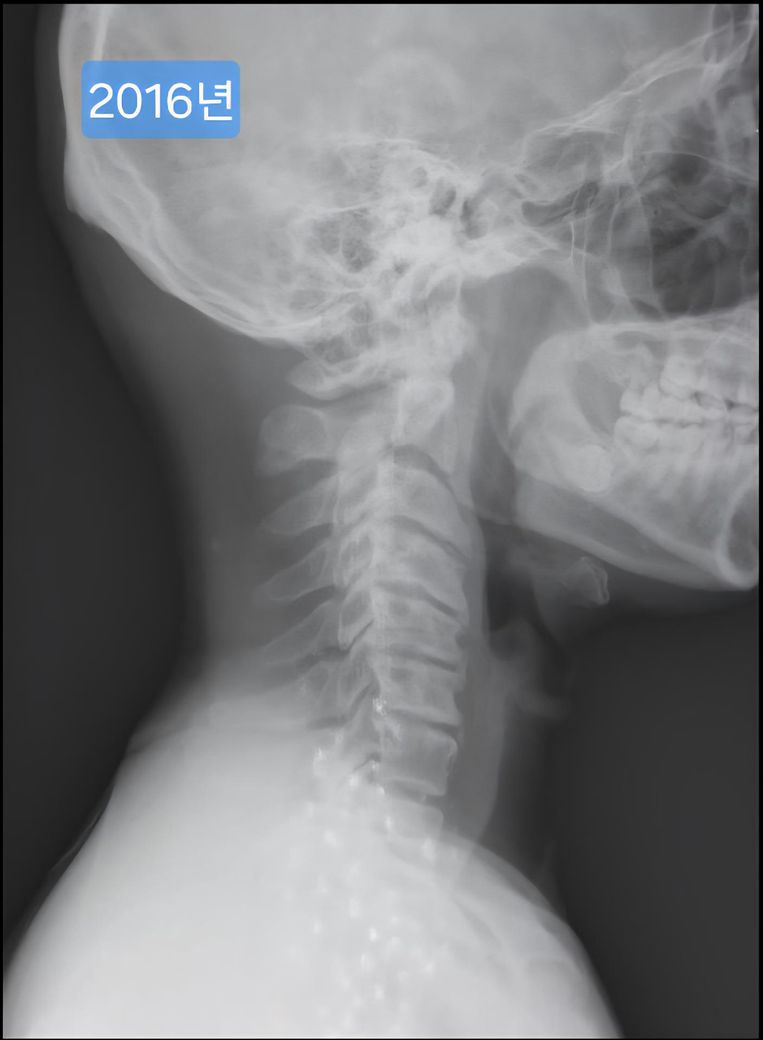

목 엑스레이 사진입니다. 많이 심각한걸까요?

오늘 찍은 2025년도 엑스레이와 9년전 사진을 업로드 해 드리겠습니다.

(이미지에 좌측상단에 해당연도 표시했습니다.)

1. 2016년과 2025년도 목이 상태가 많이 변했나요?

제가 보기엔 9년전에도 경추사이 간격이나 일자목이나 비슷한듯 보여서요.

->우선 사진상으로 봤을 땐 과거에도 충분히 경추 사이의 간격이 좁고, 목의 커브는 C자의 만곡 보단 일자목과 비슷해보이며 시간이 지나면서 누구나 겪는 퇴행성의 과정으로 보여집니다.

9년 전과 비교했을 때 경추 간격과 일자목 형태가 크게 달라진 것 같지 않아 상태가 오래 유지 된 것으로 보입니다. 오랫동안 비슷한 형태라면 큰 통증이나 신경 증상이 없다면 생활에 지장을 주지 않는 범위일 수 있습니다.